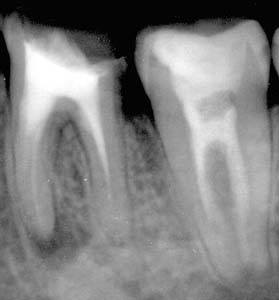

Для уточнения диагноза необходима дентальная рентгенография. Гранулема на рентгеновском снимке представляет собой тень округлой формы в апикальной зоне. Она может соприкасаться с корнем или формировать «шапочку». По мере прогрессирования заболевания все более заметными становятся зоны отсутствия костной структуры с ровными контурами. С помощью рентгенографии проводят дифференциальную диагностику гранулематозного периодонтита с другими стоматологическими заболеваниями. Хронический пульпит и средний кариес не дают никаких отклонений на рентгенограмме. Фиброзный периодонтит характеризуется расширенной периодонтальной щелью. На рентгенограмме пациента с гранулирующим периодонтитом выражены участки деструкции костной ткани с размытыми рваными краями. При корневой кисте отмечается очаг распада костной ткани более 1 см с четкими ровными краями. Чувствительность зуба у пациента с гранулематозным периодонтитом при электроодонтометрии наступает в диапазоне от 100 до 120 мкА, что соответствует некрозу пульпы.